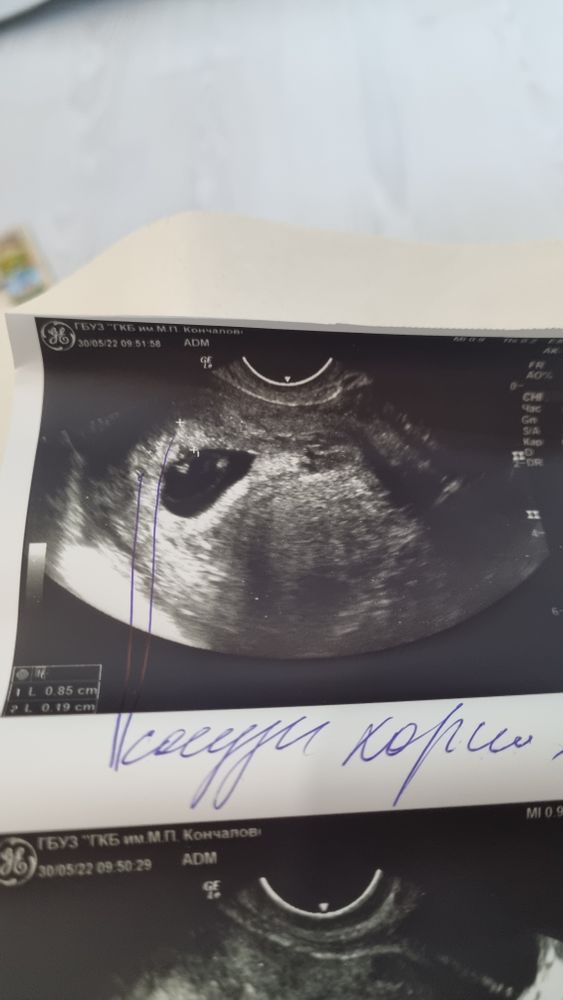

Узи 8 недель

Врач-узист внесла свою ложку дегтя: на узи обвела сосуды хориона, сказав что это либо кисты, либо сосуды хориона, либо мой варикоз, главное чтобы не росли.